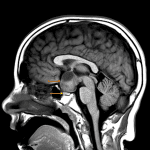

Indication: Precocious puberty

- Suprasellar mass measuring 3.5 x 2 x 3.3 cm with heterogeneous internal T1 and T2 signal

- Nodular enhancing component superiorly measuring up to 1.8 cm

- The optic chiasm appears to be incorporated within the mass

- The pituitary gland is visualized separate from the mass

- The mass contacts the right A1 ACA segment, both supraclinoid internal carotid arteries, the basilar artery, the posterior communicating arteries, and the P1 segments of both PCAs

- The mass also contacts and deforms the floor of the third ventricle

Optic pathway glioma (pilocytic astrocytoma)